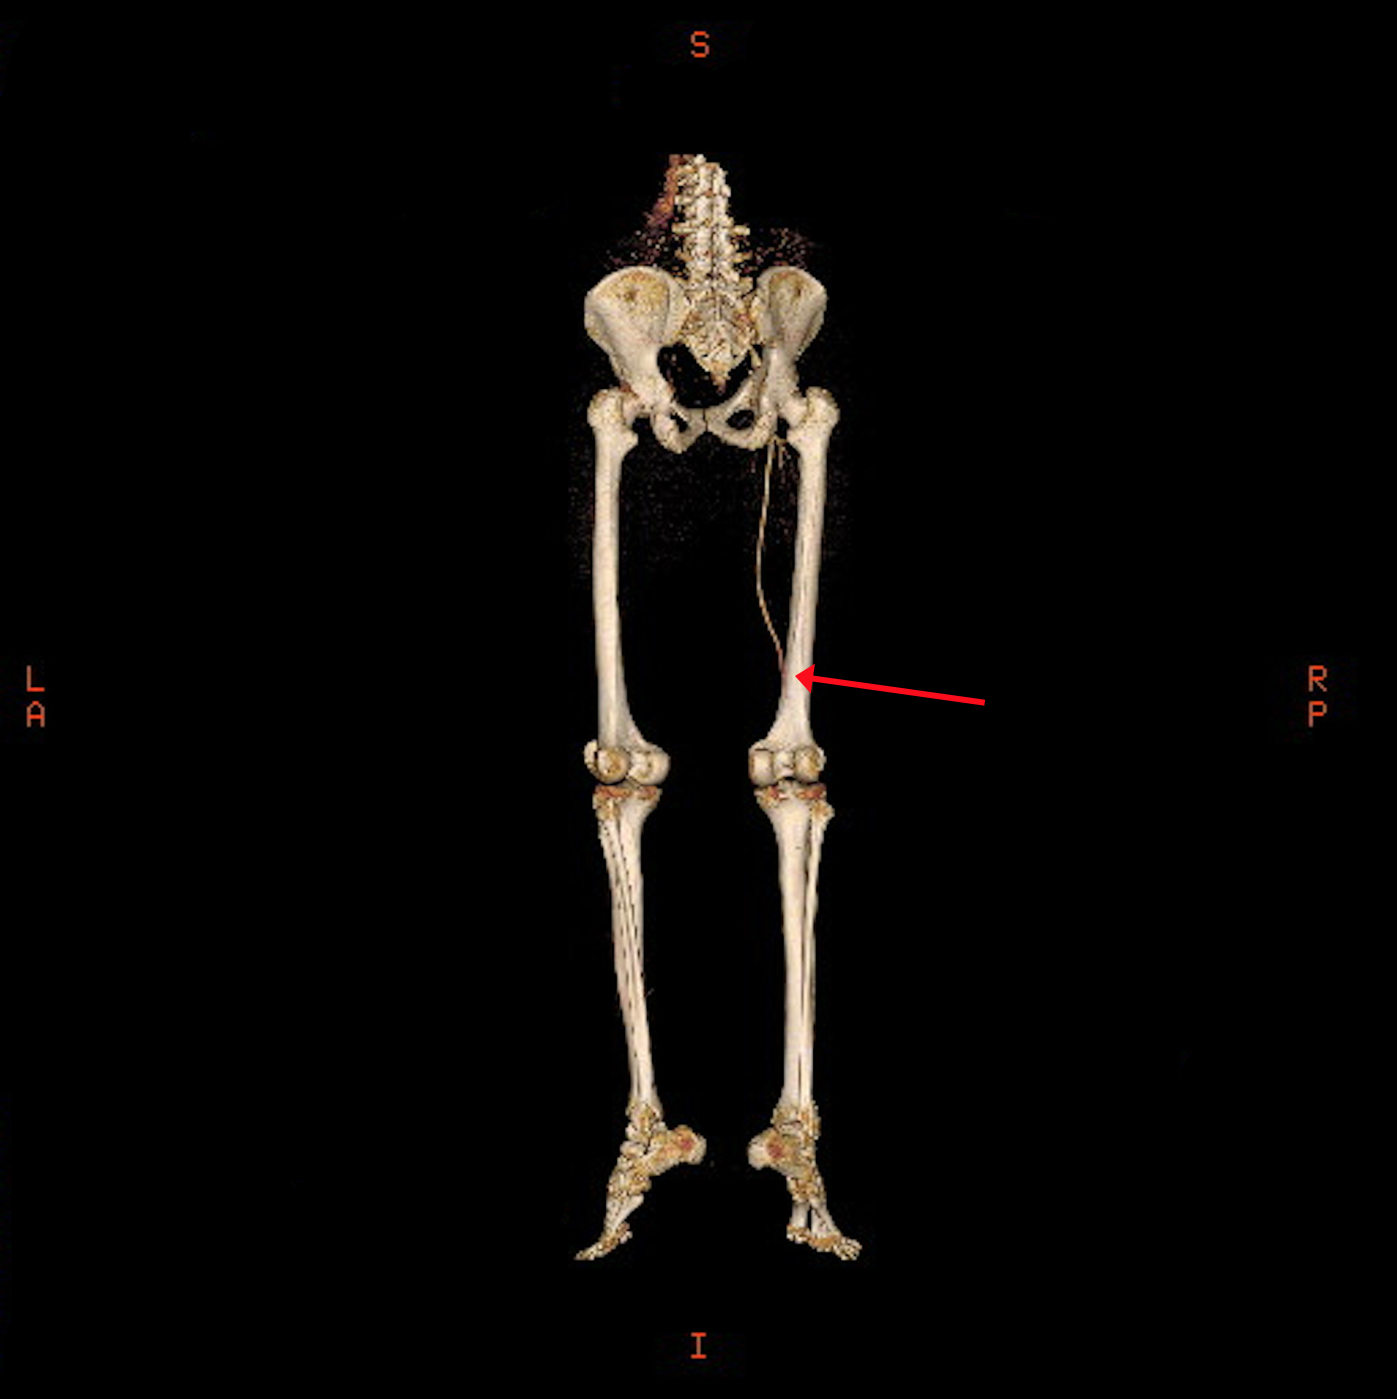

The CT angiogram and CT chest aortogram revealed a hypodense filling defect in the aorta below the level of the renal arteries causing partial occlusion of the aorta (Figure 2). There was complete occlusion of the left common iliac artery just after bifurcation of aorta extending up to the common femoral artery (Figure 3). There was good contrast uptake in right common iliac artery, femoral artery, superficial femoral artery up to the popliteal artery then the abrupt cut off of right popliteal artery present with no contrast filling seen in the distal arteries (Figure 4 and 5). Additionally, multiple bilateral wedge shaped infarcts seen in both the kidneys and the spleen (Figures 6). Chest x-ray was normal.

Figure 3: 3-Dimentional Angiogram showing a complete obstruction of the left iliac artery.

Figure 4: 3-Dimentional Arteriogram showing complete obstruction of the right popliteal artery.

In earlier literature, reports of cerebral, renal and cardiac complications of AM have been documented, [5,6]. Hofer A et al. [3] has reported a case of bilateral lower limb weakness caused by complete infrarenal occlusion of abdominal aorta due to embolization of cardiac myxoma. That mass was removed by laprotomy [3]. In our case the patient present with lower limb weakness and CT angiography showed partial occlusion of aorta.